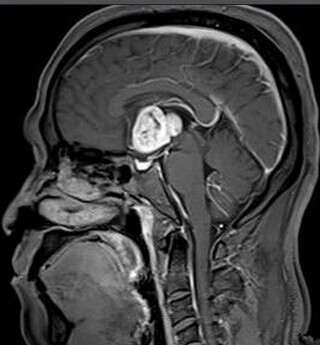

患者:男,50岁,记忆力下降1月余,双眼视力下降,反应减慢。

【正确答案】D 胶质瘤(第三脑室脊索样胶质瘤)

第三脑室脊索样胶质瘤的特征性表现是:

(1)见于成人,边界清楚,位于第三脑室前部;

(2)T1WI上为低信号,T2WI上呈明显高信号;

(3)增强后明显强化;

(4)肿块累及视交叉及下丘脑,但不浸润周围脑实质。